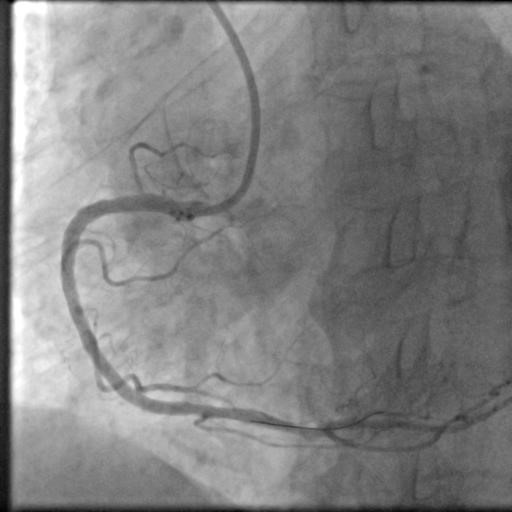

17时30分,陈奶奶已躺在导管室的手术台上,副主任医师朱劲草与王东一起为她进行血管造影。高清的影像图令所有人都禁不住倒吸一口冷气——右冠脉近中段起全部闭塞,仅可见75px左右血管,左冠前降支回旋支也有多处重度病变!

“赶紧开通右冠放支架。”在朱劲草冷静果断的判断下,心内团队成员各就各位,迅速开始了相应处理。

右冠动脉经过及时处理后,陈奶奶如今气色好多了。“非常感谢心内科的医生护士救了我家老伴儿”,吴爷爷满脸喜悦,“不久前我自己才在上海做了支架手术,没想到老伴儿也出了问题,康华医院的医生护士都很好,等老伴儿恢复下身体,之后左边冠脉的手术还在这儿做。”